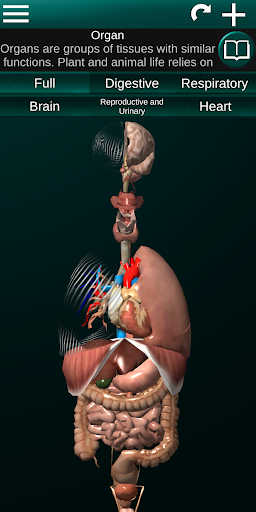

Internal Organs in 3D Anatomy لـ Vodafone Smart N9 Lite

(الأجهزة الداخلية في)

Internal Organs 3D Anatomy 3.4

يمكنك هنا تنزيل ملف حزمة تطبيق أندرويد "Internal Organs 3D Anatomy" الخاصة بجهازVodafone Smart N9 Lite مجانًا، نسخة ملف حزمة تطبيق أندرويد - 3.4 للتحميل على Vodafone Smart N9 Lite اضغط ببساطة على هذا الزر. إنه سهل وآمن. نحن نقدم فقط ملفات حزمة تطبيق أندرويد الأصلية. إذا انتهكت أية مواد موجودة في الموقع حقوقك قم بإبلاغنا من خلال